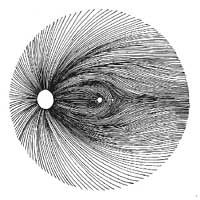

Očekávali byste protažení exkavace k hornímu pólu terče, jak nám ukazuje tento snímek z tomografu HRT II.